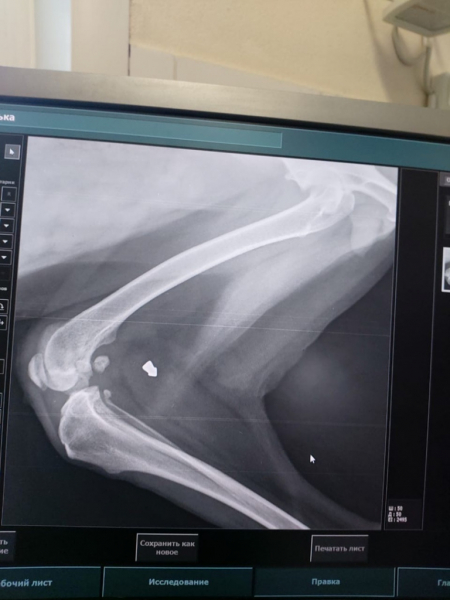

Инородное тело обнаружили совершенно случайно— Алька вдруг перестала наступать на лапу, началась атрофация мышц. Рентген удивил, словно гром среди ясного неба.

В итоге Алька совсем перестала наступать на лапу, началась атрофация мышц. Собаку отвезли в ветклинику, где сделали рентген. Снимок был словно гром среди ясного неба. В ноге у собаки всё это время сидела пуля. «То есть все эти годы она жила с этим подарком от "добрых людей". Но проявились последствия только сейчас. Возможно, это произошло в силу возраста», — добавили в приюте. Альке потребовались обследование, операция и послеоперационный уход.